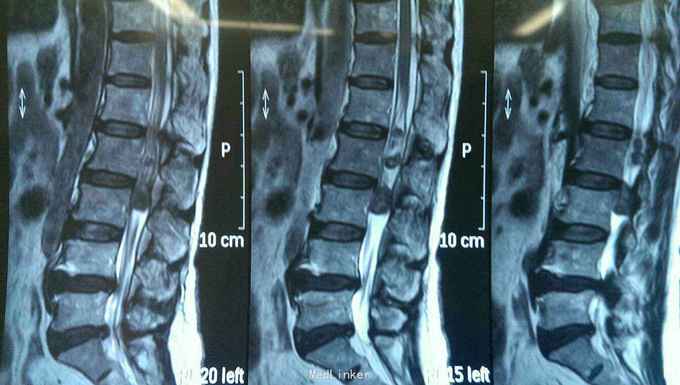

患者以腰部疼痛一年伴右侧大腿麻木两个月为主诉入院。患者入院一年前出现腰部疼痛,当时未注意。两个月前患者自诉右侧大腿麻木,运动尚可,无尿便障碍。门诊行核磁共振检查后以椎管内占位病变收入院。既往健康。

神志清楚,语言流利。颅神经检查未见异常。右侧臀部一下浅深感觉减退,肌力四级。生理反射存在,病理反射未引出。括约肌功能正常。核磁共振提示腰1--3椎管内多发病变,明显强化。

入院诊断椎管内多发占位病变,神经纤维瘤。完善术前准备后行后正中入路神经纤维瘤切除术。术中见马尾神经生长多个肿瘤,与其余神经无粘连,完整切除肿瘤。